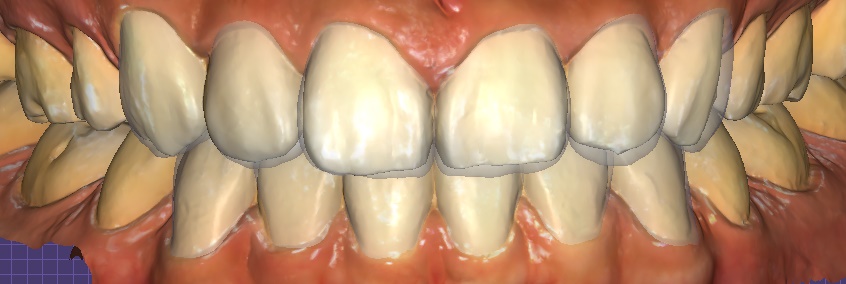

① 디지털 스캔 & 디자인

– 구강스캐너로 정밀한 데이터 채득 → 3D 디자인 및 시뮬레이션

오브제로 라미네이트 시뮬레이션